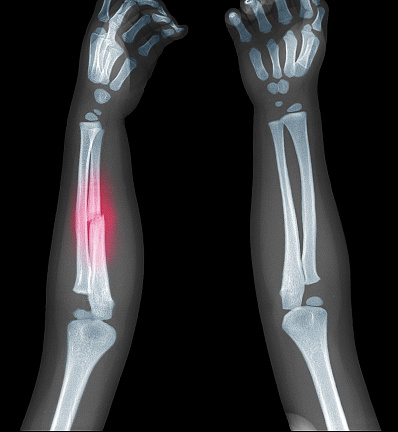

Children’s bones differ significantly from those of adults. The bones of children are still growing and contain cartilage, which makes them more flexible and prone to specific types of fractures, such as greenstick or buckle fractures. These fractures are typically less complicated but require specialized care to prevent them from affecting bone growth. The treatment approach for children’s fractures must be precise, ensuring that the bones heal in the proper alignment while minimizing the risk of growth disturbances.